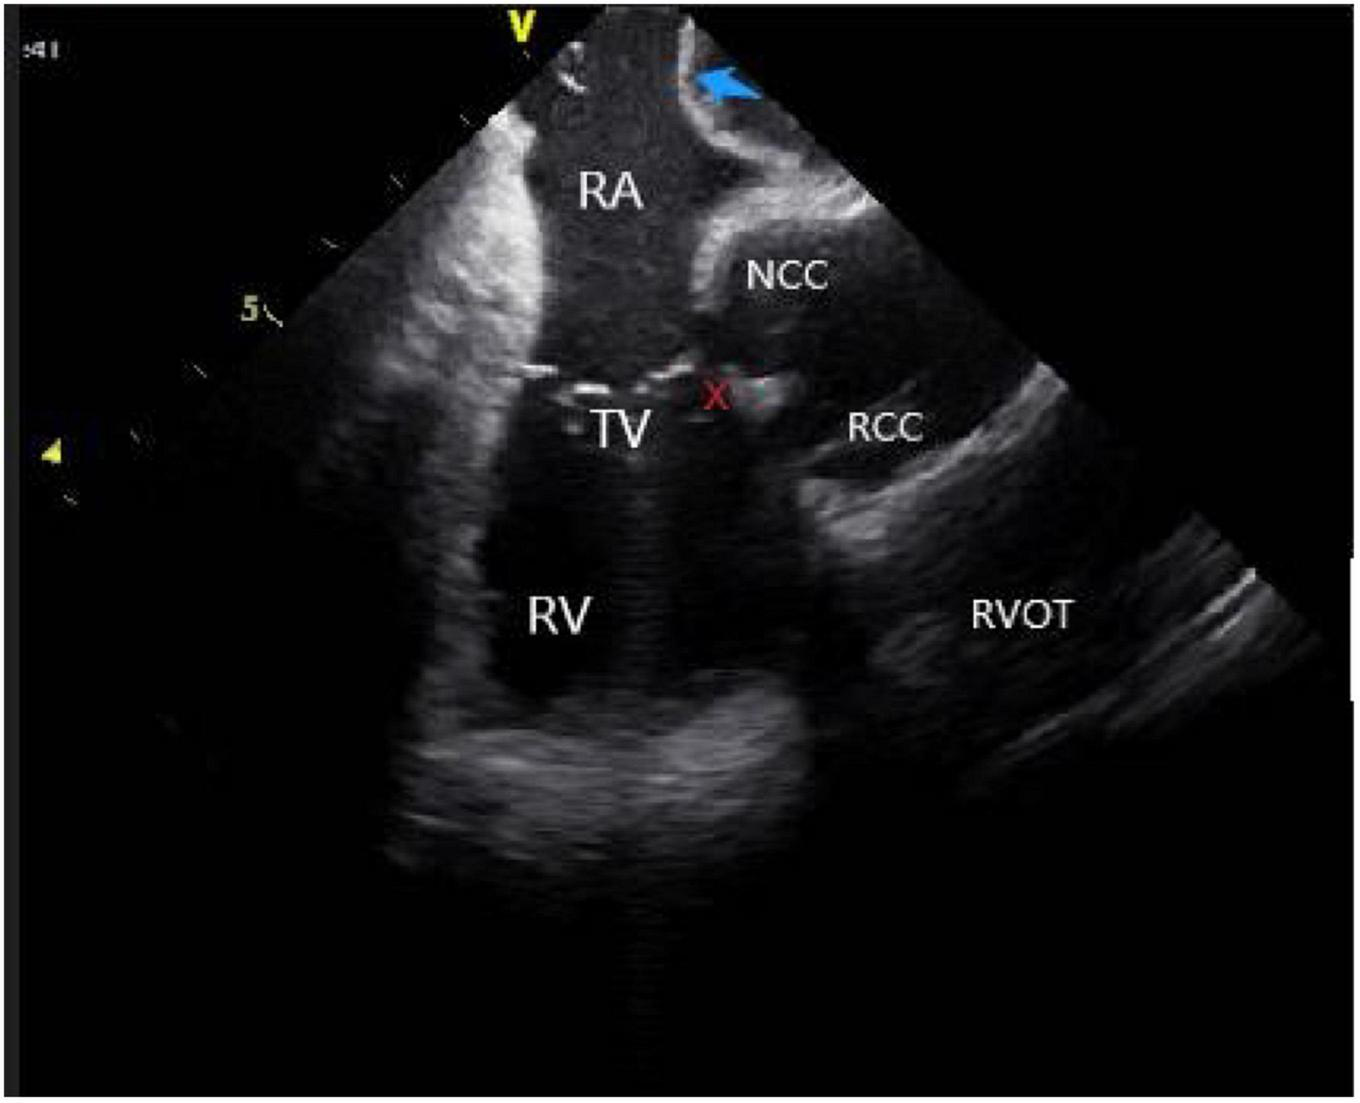

(2) Right atrium operation and view: After positioning the ICE catheter in the mid-right atrium (RA) through the inferior vena cava, the catheter was rotated so that the ultrasound probe points to the center of the tricuspid valve (TV), thereby reaching the HomeView position. This important position provided imaging of the RA, TV, right ventricle (RV), aortic long axis, non-coronary, and right coronary cusps, as well as a small part of the right ventricle outflow tract (RVOT) (Figure 1). From the HomeView position, a clockwise rotation exhibited the RV long axis model, showing the RA, coronary sinus, non-coronary and left coronary cusps, and part of the left ventricle (LV). Further clockwise rotation identified the left atrium (LA) and displayed the LA, RA, coronary sinus, left atrial appendage, mitral valve, and LV, respectively (Figure 2).

FIGURE 1

Homeview position. RA, right atrium; TV, tricuspid valve; RV, right ventricle; NCC, non-coronary cusp; RCC, right coronary cusp; AO, aortic valve; RVOT, right ventricular outflow tract; PA, pulmonary artery.